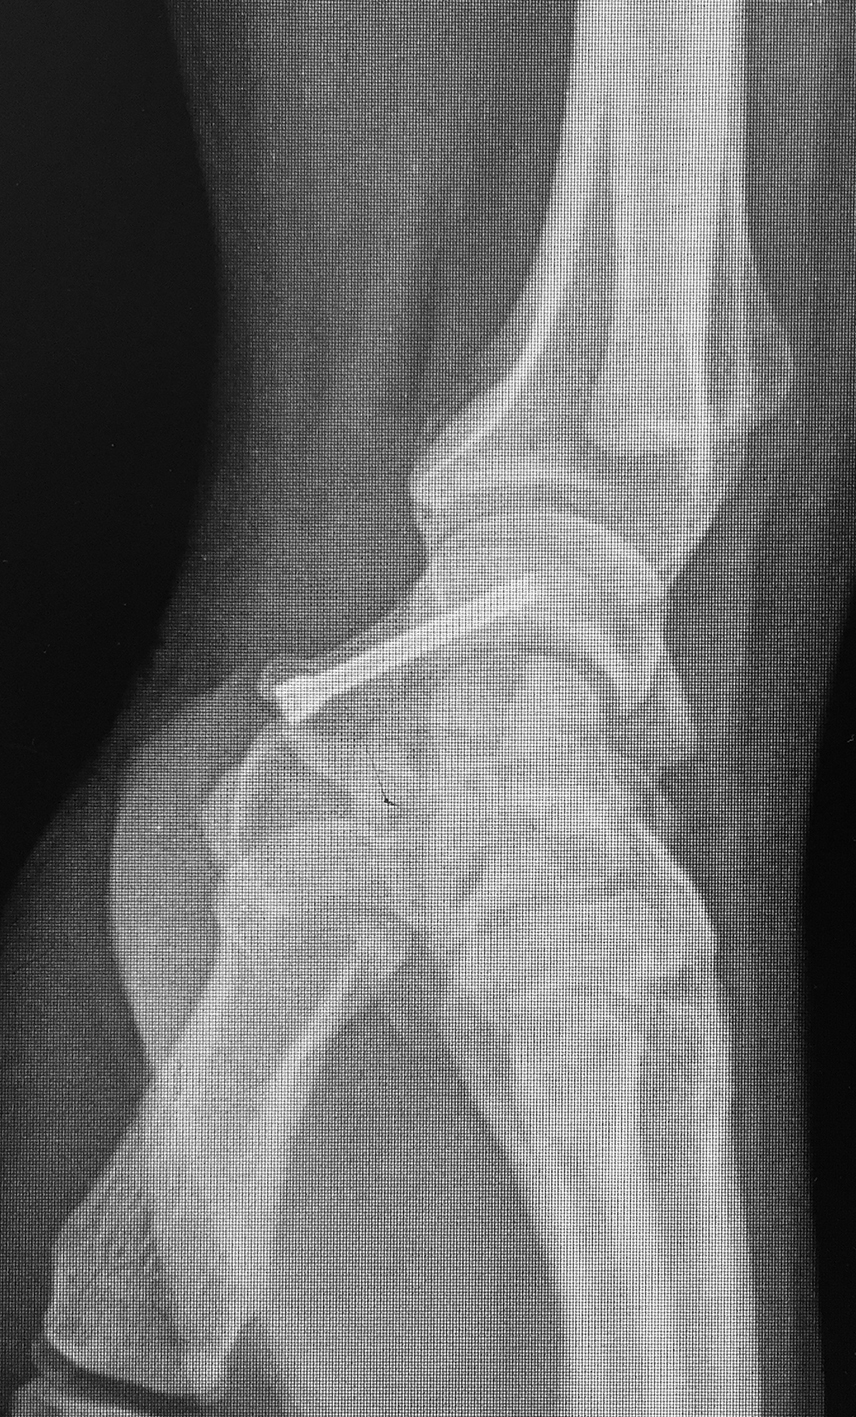

Efectuamos un abordaje volar dado que conserva la vascularización dorsal, permitía la visualización directa del foco, movilización de los polos y manejar la deformidad en joroba mediante el injerto trapezoidal (1)(11)(12). Nos centramos sobre el tendón palmar mayor, efectuando una incisión curvilínea dirigida hacia el tubérculo del escafoides. Se protegió la rama sensitiva cutánea del nervio radial y disecamos el plano superficial incidiendo la cápsula longitudinalmente sobre el eje del escafoides. Se reflejó la cápsula, se identificó el polo distal y proximal colocando dos agujas de Kirschner, a modo de joystick. Cureteamos el foco con una fresa (Figura 1). Dejando el escafoides, extrajimos un injerto cortico-esponjoso trapezoidal de cresta iliaca (Figura 2). Volviendo a la mano, distrajimos los fragmentos escafoideos y colocamos el injerto, con su base en situación volar, para extender el escafoides (1)(5)(12)(13). Colocamos otra aguja de Kirschner retrógrado como guía, y tras medir y mechar, colocamos un tornillo de compresión interfragmentaria (11), para proceder posteriormente a cerrar la cápsula y los planos superficiales. Se colocó una inmovilización con férula de yeso, incluyendo el primer dedo, que mantuvimos durante 4 semanas.

Se efectuaron radiografías dorso-palmar, lateral pre y post operatorias. Al final del seguimiento se evaluó la consolidación mediante radiografías. Se indicó un TC de puño en los pacientes como método de valoración pre operatoria y la RM cuando se sospechó un compromiso vascular del polo proximal para definir técnica quirúrgica.

La evaluación de la movilidad mostró que 5 pacientes (29,4%) tenían la movilidad completa; 11 pacientes (64,7%) la conservaron entre el 75 y el 99 % y un paciente (5,9%) entre el 50 y el 74%. No encontramos asociación estadística entre la movilidad y el retraso terapéutico (p=0,241). (Figura 3) (Figura 4) (Figura 5) (Tabla 1) (Tabla 2).

Figura 4: Caso 12

a) Radiografía de frente pre-operatoria

b) Radiografía pre-opertaoria, enfoque de escafoides

c) Radiografía post operatoria

e) 24 meses de seguimiento. Radiografía de frente

f) 24 meses de seguimiento. Radiografía de perfi

g) 24 meses de seguimiento, extensión de muñeca

h) Flexión de muñeca